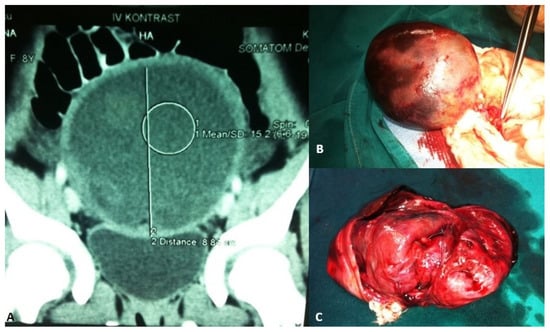

Adolescent ovaries can have several follicles at various developmental stages. The majority of ovarian cysts in adolescents are follicular cysts, which occur due to a maturing follicle’s failure to ovulate and involute. Large cysts can lead to frequent urination, constipation, or a sensation of pressure in the lower belly, whereas twisting, rupture, or hemorrhage of the cyst causes intense acute pain (Figure 2) [46].

Figure 2.

A 13-year-old adolescent presented to the emergency room because of recurrent crampy abdominal pain that lasted a short time and then subsided. She had had the symptoms for about a week. An abdominal ultrasound was performed, which showed a mass in the pelvis. (A) MSCT of the abdomen revealed a 9.1 × 8.8 cm solid cystic mass in the right ovary that was not perfused; (B) Intraoperatively, a torquing, partially necrotic tumor of the ovary was noted; (C) Pathohistological findings were consistent with a mature teratoma of the right ovary. Source: Archive of the Department of Pediatric Surgery, University Hospital of Split.